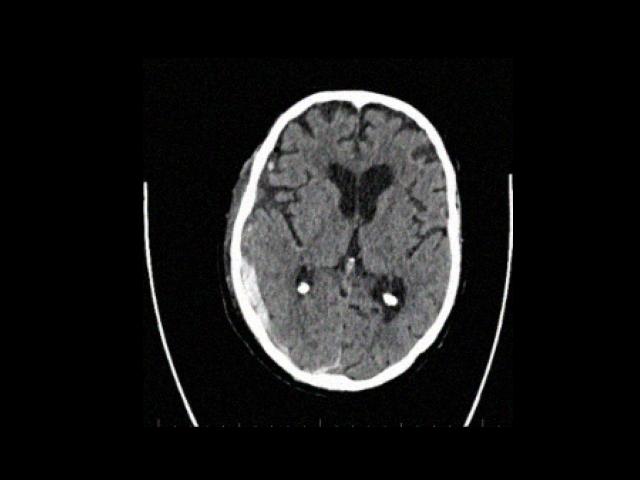

Sample Gallery